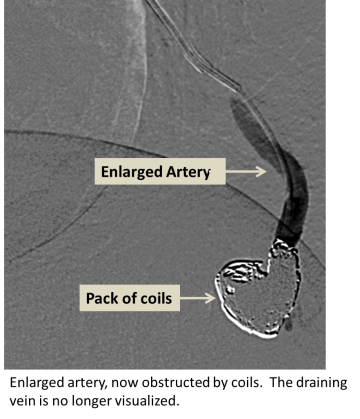

Enlarged artery obstructed by coils. The draining vein is no longer visualized.

• Pulmonary AVM embolization

• Angiography (X-ray with contrast agent to visualize and treat the abnormal blood vessels)